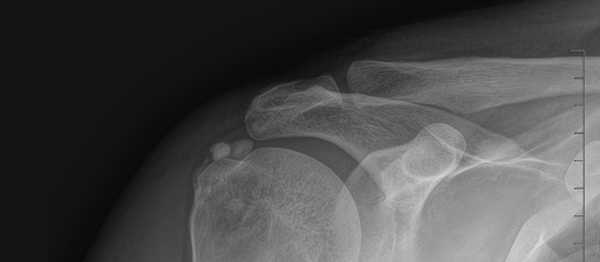

석회쇄석흡인술 페이지 정보 작성자최고관리자 등록일 2025-02-25 17:45 조회30 본문 치료 증상 자고 나서 팔을 들기 힘들 정도의 심한 어깨 통증 나이 / 성별 45세 / 남성 치료내용 석회쇄석흡인술 후 호전 치료기간 2024-09-12 ~ 2024-12-18 null 목록 이전글석회쇄석흡인술 25.02.26 다음글석회쇄석흡인술 25.02.25 댓글 0 댓글목록 등록된 댓글이 없습니다.